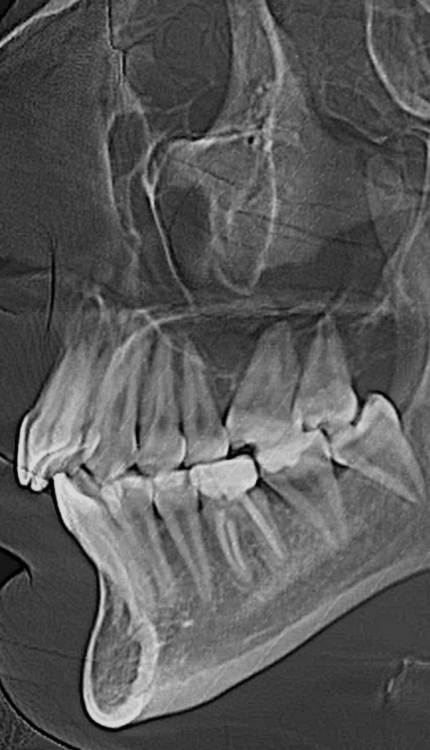

На консультации у ортодонта был поставлен диагноз : Нейтральное соотношение челюстей с тенденцией к дистальной окклюзии. Глубокая резцовая окклюзия.

Врач предложил установить безлигатурную брекет систему , вообщем-то , я была согласна, но замена имплантами 2 отсутствующих шестерок  меня немного пугала.т.к шестерки были удалены достаточно в раннем возрасте соседние зубы заняли их место и визуально это было почти не заметно .При всем  этом , у меня есть все восьмерки ,соответственно , перед установкой БС их так же нужно будет удалить(

Так вот , у меня возник вопрос, возможно ли стянуть  зубы в ровную окклюзию при помощи БС вместе  с 7(Заменяющей место 6) и 8 ?

То есть , возможно ли как-то восстановить центральную окклюзию и, в целом, сделать красивую улыбку не применяя имплантацию ?).